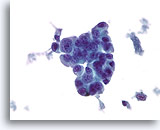

Atypische ductale hyperplasie, Borst FNA, Celblok.

Dit plaatje van de naaldspoeling van de patiënt in afbeelding 15 toont een uniforme populatie van vrijelijk stratificerende ductale cellen met een uniforme spreiding van kernen, afwezigheid van een stromingspatroon en de aanwezigheid van uniformere ronde ruimten in het kleinere fragment.

10X

Atypische ductale hyperplasie, Borst FNA, Celblok.

Dit plaatje van de naaldspoeling van de patiënt in afbeelding 15 toont een uniforme populatie van vrijelijk stratificerende ductale cellen met een uniforme spreiding van kernen, afwezigheid van een stromingspatroon en de aanwezigheid van uniformere ronde ruimten in het kleinere fragment.

10X

Atypische ductale hyperplasie, Borst FNA, Celblok.

Let op de gelijkvormigheid van de cellen (dit duidt op een afwezigheid van myoepitheliale cellen) en de uniforme spreiding van cellen zonder gedeelde polariteit.

40X

Atypische ductale hyperplasie, Borst FNA, Celblok.

Let op de gelijkvormigheid van de cellen (dit duidt op een afwezigheid van myoepitheliale cellen) en de uniforme spreiding van cellen zonder gedeelde polariteit.

40X